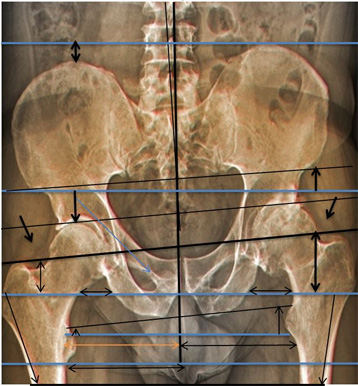

Becken Bild 1

Anhand der Original Aufnahmen werden Spannungsbedingte Ausweichhaltungen auf den folgenden Seiten sichtbar gemacht.

Aufnahme zeigt eine Verdrehung der linken Seite, anhand der Beckenlöcher.

Zudem muss das Becken seitlich verschoben sein.

Sichtbar anhand der Beinstellungen und der Verdrehung des Schenkelhalses.

Weiter wird ersichtlich, dass links das Becken hochgedrückt wird.

Eindeutig am Beckenspalt zu erkennen, das der Oberkörper nach links ausweicht und somit das Becken in der Höhe verzieht.

Auch drückt es oberhalb der Hüftkugel rechts das Becken über den Zug der seitlichen Oberkörper Haltung hoch und verzieht das Becken.

1.2

Wurde ein neues Hüftgelenk eingebaut, wegen den Schmerzen in der Leiste.

1.3

Nun sieht man, dass die Bein- und Gelenk-Stellung nicht übereinstimmt.

Die Schmerzen sind geblieben.

Abbildung Hüft / Teil Rücken / Teil Beine von hinten aufgenommen

Hüft mit Strichen Pfeilen Kreise sichtbar gemacht

Oberkörper weicht trotz Hüftgelenk Ersatz blau eingesetzte Striche aus.

Anhand der Gesässfalten wird auch der Beckentiefstand ersichtlich.

Über die Grüne Linie sieht man wie die rechte Seite geknickt wird.

Auf der linken Seite wird die Überdehnungsspannung sichtbar.

Würde die Ganz-Körper-Statik Vermessung eingesetzt, würde die Diagnose schnell und präzise die Ausweichhaltungen aufzeigen.

Würde die Ganz-Körper-Statik Vermessung bei den bildgebenden Verfahren eingesetzt, könnten Fehldiagnosen verhindert werden. Dies würde die Ursache der Skelett Ausweichhaltungen als Ursache der Muskelfehlspannungen aufzeigen.

1.7

Trotz dem wurde das andere Hüftgelenk auch noch ausgewechselt.

Trotz Operationen sind die Schmerzen geblieben.

Beachtet man das Becken und die Gelenk-Stellungen sieht man nun auf der rechten Seite eine Verdrehung des Beckenlochs.

Der Beckenspalt ist immer noch hochgezogen. Durch die Verdrehung quetscht nun die linke Seite.

Man hat die Belastung verschoben.

Bei der Statik Kontrolle wurde der Beckentiefstand und der damit verbundenen seitlichen Oberkörper- Ausweichhaltung nicht beachtet.

1.8

Würde die Ganz-Körper-Statik Vermessung bei den bildgebenden Verfahren eingesetzt, könnten Fehldiagnosen verhindert und zudem viele Kosten gespart werden. Dies würde die Ursache der Skelett Ausweichhaltungen als Ursache der Muskelfehlspannungen aufzeigen.

Um auch die Ursache der Beschwerden aufzudecken, wird der Einbau der Ganzkörperstatik und des Hebelgesetzes benötigt, damit auch reproduzierbar die Gesamtkörperstatik berücksichtigt werden kann.